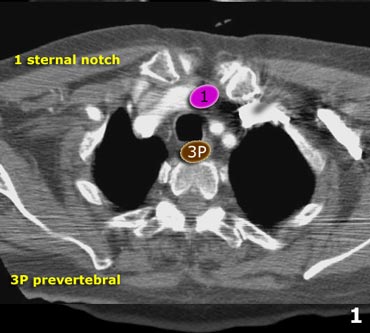

Mediastinal Lymph Node Map - Axial CT of Lymph Nodes